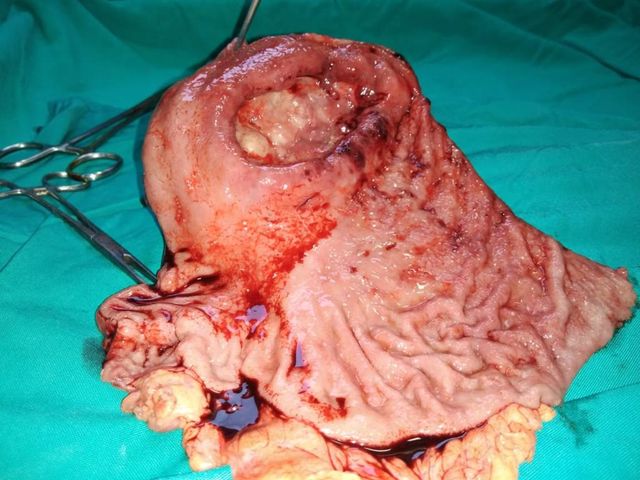

A rare case of gastric schwannoma masquerading as a GIST - 52 year old lady presented with massive GI bleed

A rare case of gastric schwannoma masquerading as a GIST. 52 year old lady presented with massive GI bleed and severe anemia Hb 5.0 gm. Her CT scan and endoscopy revealed a exophytic lesion 10 x 12 cmof gastric body with a ulceration in stomach. She underwent a lap assisted subtotal gastrectomy with a diagnosis of a GIST. Post operative immunohistochemistry revealed a gastric schwannoma. Gastric schwannoma is a very rare mesenchymal tumor arising from the nerve plexus of gastric wall . Unlike gastric GIST of this size >10 cm which are usually the rare malignant schwannoma are entirely benign with excellent long term prognosis.